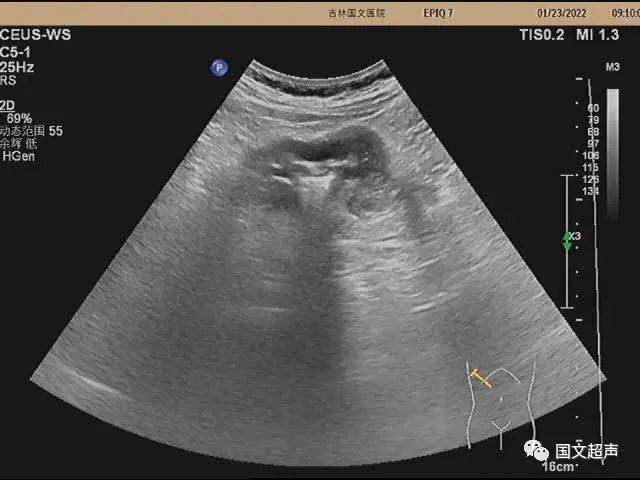

超聲檢查:右側(cè)結(jié)腸肝曲處腸壁不均勻性增厚,走行僵直,蠕動不佳,呈“假腎征”,術(shù)后病理:右側(cè)結(jié)腸低分化腺癌。